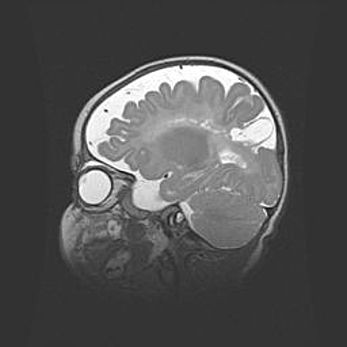

Множественные кисты обоих полушарий головного мозга, наибольшая из них в правой затылочной области. Ассиметричная атрофическая гидроцефалия.

Возраст: 7 месяцев

Вес: 5660 г

Пол: мужской

Окружность головы: 41,5 см

Срок гестации: 28-29 недель

Кисты головного мозга развиваются в результате многоочаговых некрозов вещества мозга и возникают вследствие перенесенной перинатальной инфекции, менингитов, энцефалитов, асфиксии, родовой травмы, расстройств мозгового кровообращения различного генеза. Образованию кист в веществе головного мозга плодов и новорожденных способствуют такие факторы, как высокое содержание в нем воды, недостаточная (или отсутствие) миелинизация и слабая астроглиальная реакция на повреждение.

Кисты могут сочетаться с гидроцефалией и другими поражениями головного мозга.